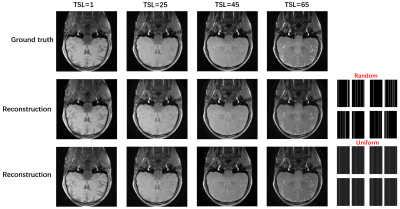

A schematic diagram of the bidirectional process is given in Fig. 1. The weighted images corresponding to different TSL are perturbed with Gaussian noise of differentintensities. The results in Fig.2 show that the uniform pattern has a certaintranscendence relative to the random pattern in terms of artifact-free. From T1rho maps by exploiting curve fitting, the proposed method is capable of quantification of T1rho relaxation times in uniform pattern with 8-fold acceleration.

Fig. 2 Sampling generation results of TSL-weighted images with different sampling patterns (variable density and uniform with 18 ACS) at 8x acceleration factor. The sampling pattern for each group of T1rho-weighted plots is given at the bottom right.